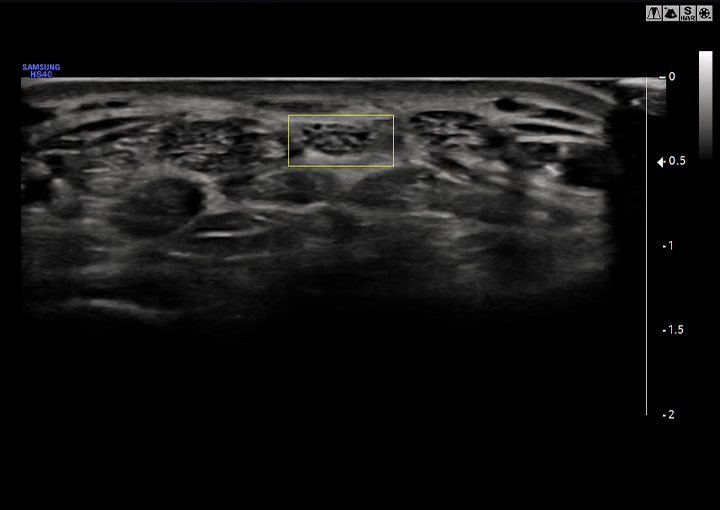

NerveTrack

Detect the location of nerve area in real-time

Mit NerveTrack können während einer Ultraschalluntersuchung in Echtzeit Nervenbereiche erkannt werden. Die Position des Nervenbereiches wird dabei mit einer Box hervorgehoben, um für eine direkte Erkennbarkeit zu sorgen.

• ※ Dieses Video oben dient nur zur Erläuterung der NerveTrack-Funktion.